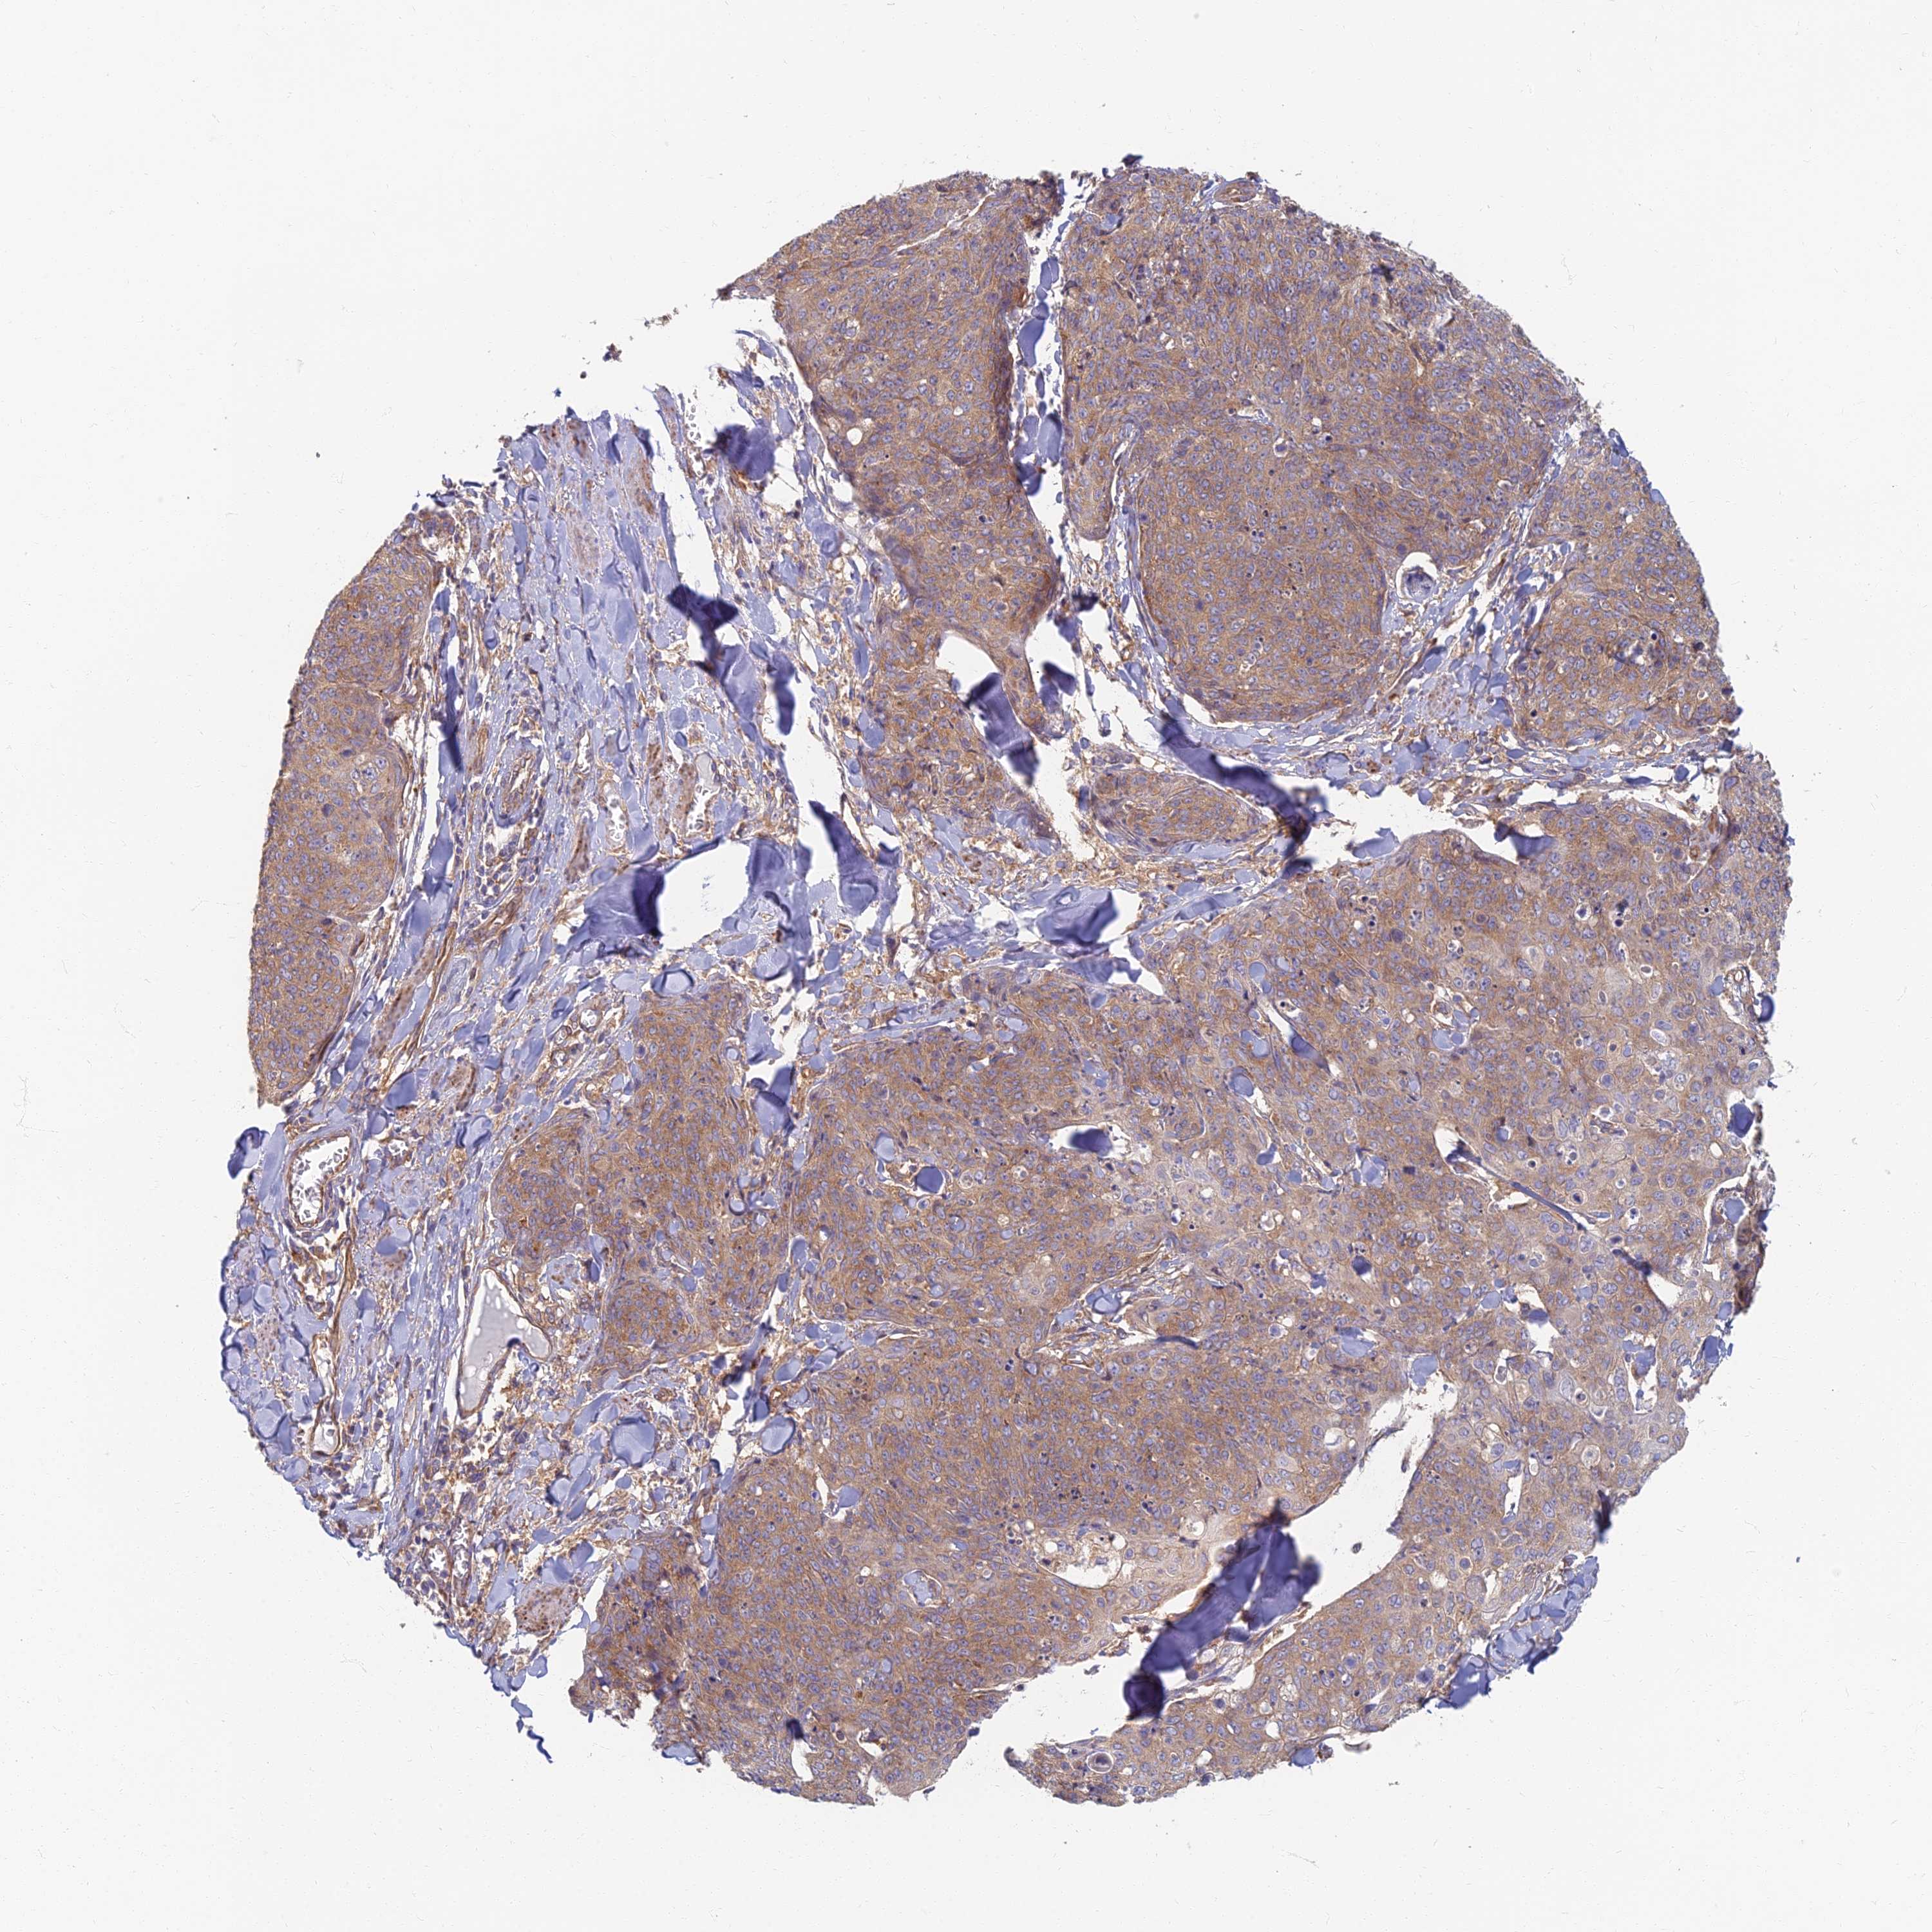

SKIN CANCER - Protein expressioni

A mouse-over function shows sample information and annotation data. Click on an image to view it in a full screen mode. Samples can be filtered based on level of antibody staining by selecting one or several of the following categories: high, medium, low and not detected. The assay and annotation is described here.

Antibody stainingi

Antibody staining in the annotated cell types in the current human tissue is reported as not detected, low, medium, or high, based on conventional immunohistochemistry profiling in selected tissues. This score is based on the combination of the staining intensity and fraction of stained cells.

Each image is clickable and will lead to virtual microscopy that enables deeper exploration of all samples and also displays staining intensity scores, fraction scores and subcellular localization as well as patient and tissue information for each sample.

Antibody HPA044878

Staining

High

Medium

Low

Not detected

Intensity

Strong

Moderate

Weak

Negative

Quantity

>75%

75%-25%

<25%

None

Location

Nuclear

Cytoplasmic/membranous

Cytoplasmic/membranous,nuclear

Basal cell carcinoma